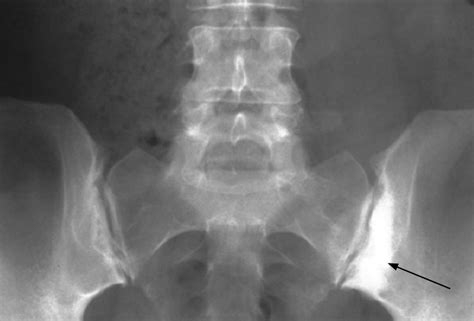

• Joint Space Width: A narrowing of the joint space often indicates wear and tear or degenerative joint disease.

• Sclerosis: This refers to an increase in bone density around the joint, which is a common response to chronic stress or inflammation.

• Erosions: Small "nibbles" in the bone surface, which are highly suggestive of inflammatory arthritis.

• sacroiliac joint x ray abnormalities

• sacroiliac joint x ray abnormal